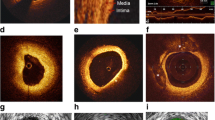

Cardiac magnetic resonance

Cardiac magnetic resonance (CMR) represents a useful resource in the assessment of both structural and functional changes, providing also information regarding the composition of myocardial tissue. In fact, in patients with insufficient acoustic window, CMR is an alternative to echocardiography to assess cardiac chamber volumes and function as well as to exclude acute cellular rejection. In fact, its role in HTx patients has been more intensively studied with regards to acute cellular rejection, since first studies in CAV showed low sensitivity [838584] (Fig. 6). First encouraging data derive from the analysis of the peak filling rate, which is an estimate of diastolic function, whose values were lower in advanced CAV rather than in earlier stages. Indeed, early diastolic strain rate impairment was successively associated to microvascular dysfunction [86], while LVEF, stroke volume and cardiac output may be found normal either in early and late stages [87]. These results might hint that diastolic dysfunction in this population might be more sensitive than indexes of systolic function for the precocious detection of CAV.

Invasive coronary angiography vs cardiac magnetic resonance. Evidence of diffuse wall thickening in the distal left anterior descending artery (LAD) and stenosis in the left circumflex artery (LCx), as revealed by invasive coronary angiography (ICA). Cardiac magnetic resonance (CMR) did not detect any of these defects. CMR, cardiac magnetic resonance; ICA, invasive coronary angiography; LAD, left anterior descending artery; LCx, left circumflex artery. Adapted from Nunoda S et al., 2010 (10.1253/circj.cj-09–0800) [84]

Microvascular disease can be assessed by stress perfusion CMR, through the estimate of myocardial perfusion reserve (MPR), even though first results were not encouraging in detecting CAV [84], later ones showed promising findings due to the fact that diffuse CAV can affect the microvasculature independent of lesions in the epicardial vessels. In fact, further and more detailed studies about MPR reported a lower index in those with an IMT ≥ 0.5 mm as found with IVUS, with a moderate inverse relationship [88]. MPR ≤ 1.68 has a 100% sensitivity and 100% NPV in detecting CAV, but still has low specificity (63%). This index, as well as GLS, is altered years after HTx, and should be attributable to CAV rather than to fibrosis or graft rejection [89]. Also, MPR assessed by multiparametric CMR outperformed ICA for the detection of moderate CAV in a study by Miller et al. [90].